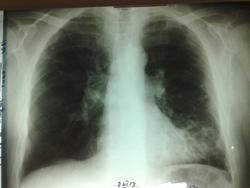

Снимки его за 7.6.13: Та же "мазня" слева

А слева мазня и раньше была, и она не прогрессирует. Условия съёмки разные. Я расцениваю  эту картину, как остаточные явления ранее перенесенной пневмонии в S 9 слева.